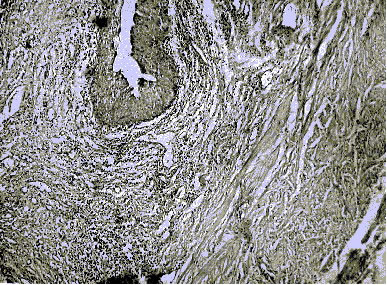

41 сутки (Склероз подслизистого, очаговая гиперплазия

уротелия с фокусами плоскоклеточной метаплазии)